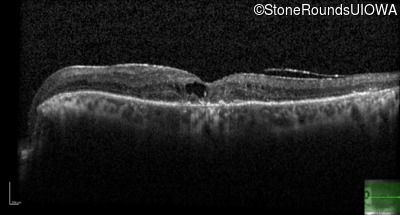

Age at visit: 69 years

Age at visit: 70 years

Age at visit: 72 years